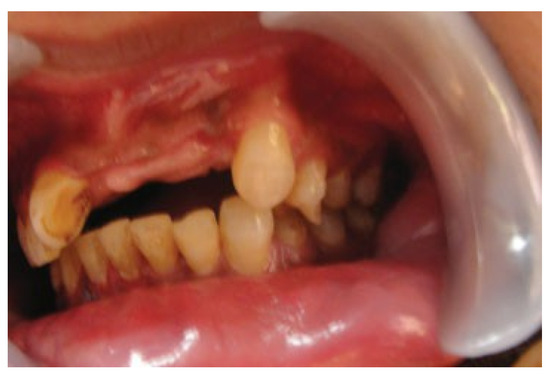

:1. Case Report